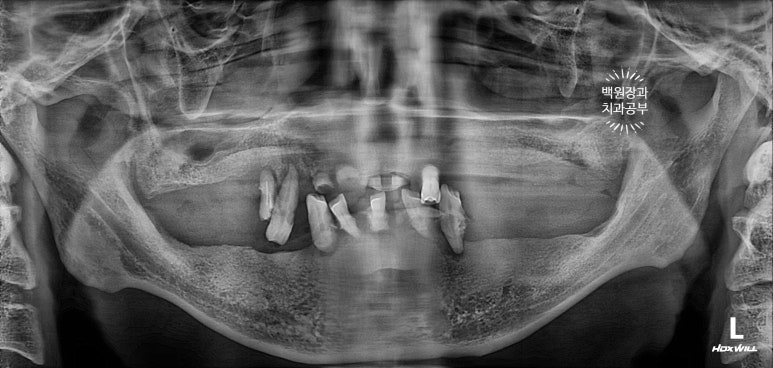

40대 남자 환자분이었는데... 상당히 심각해보이는 치과용 파노라마 사진...

중구 신당동에서 내원해주신 분이었습니다...